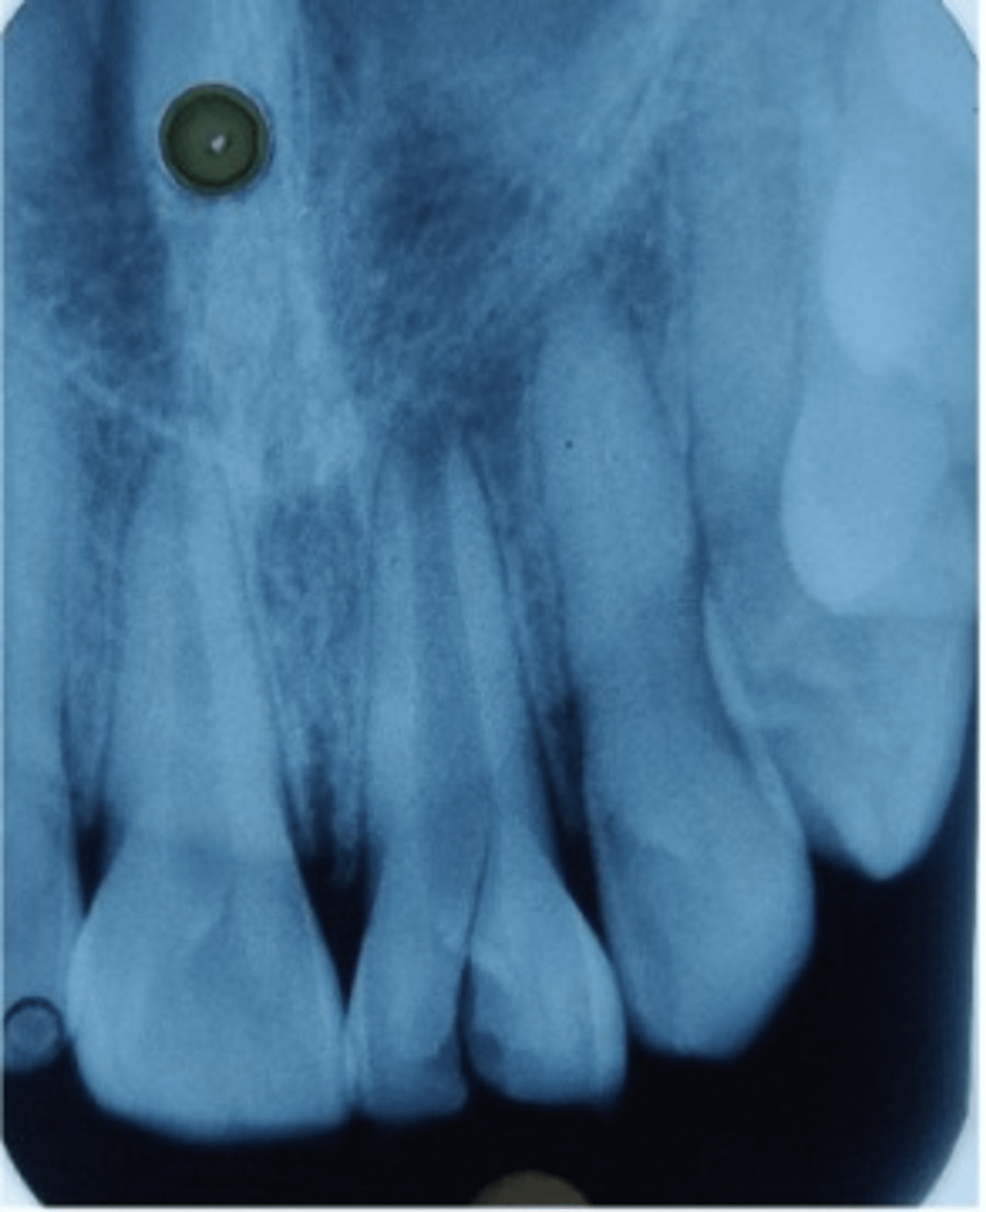

(A) Preoperative radiophotographs showed tooth 21 having open apex Open Apex Tooth Definition in children, where the tooth apex is open, the pulp will often revascularize and the tooth remains vital. the open apex can be defined as an unusually wide apical foramen of a root, making it challenging to prepare an apical. Proper diagnosis and treatment planning. an ‘open apex’ is found as a developmental stage in the permanent. Open Apex Tooth Definition.